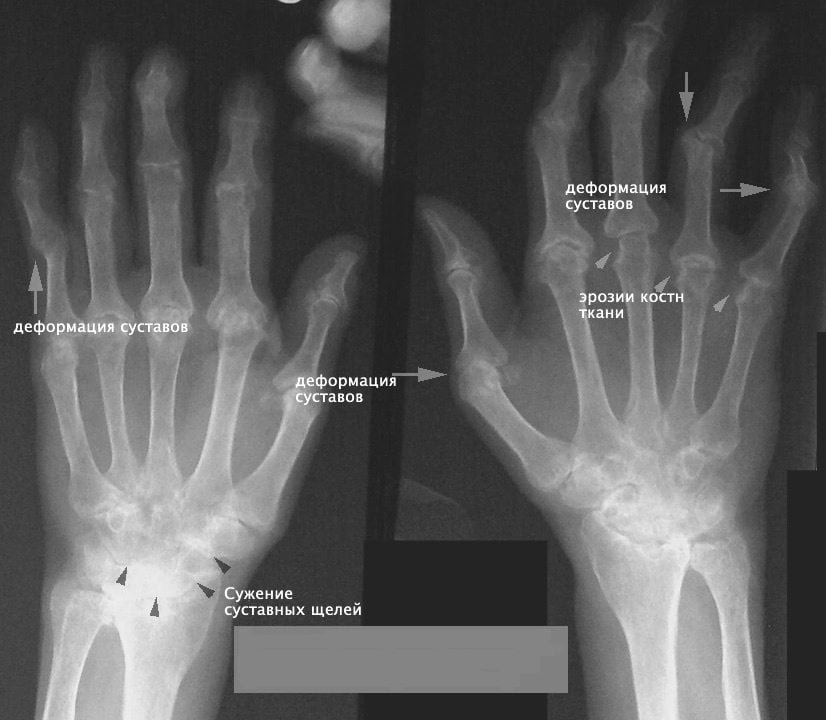

На этом этапе хрящ почти полностью разрушен на опорных поверхностях. Появляются первые костные наросты, хорошо заметные на рентгеновских снимках, и явное сужение суставной щели. Иногда остеофиты можно прощупать самостоятельно. Боль становится хорошо ощутимой, практически ежедневной. При движениях больной слышит отчетливый хруст. Руки устают быстрее, чем раньше. Полное выздоровление при артрозе лучезапястного сустава 2 степени уже невозможно, но лечение сильно улучшает качество жизни пациента, поддерживает мобильность в суставе.

- I стадия. Характеризуется незначительным ограничением подвижности и болевым синдромом. На рентгеновском снимке визуализируются сужение суставной щели и заострение краев поверхностей сочленений;

- II стадия. Усиление основных симптомов: боли умеренной интенсивности, более ощутимое ограничение подвижности. На снимке врач отметит более выраженное сужение суставной щели, формирование остеофитов по поверхностям сочленения;

- III стадия. Характеризуется значительным ограничением подвижности в запястье, сопровождающимся сильными болями в суставах рук. На рентгеновском снимке суставная щель полностью отсутствует, видны кистовидные костные разрастания, видимая деформация сустава.

Проведение визуальной диагностики лучезапястного сустава помогает обнаружить стадию развития заболевания. Рентгенография применяется, если врач при визуальном осмотре обнаружил деформации, вывихи, а также, если в карте есть сведения о переломах, растяжениях.